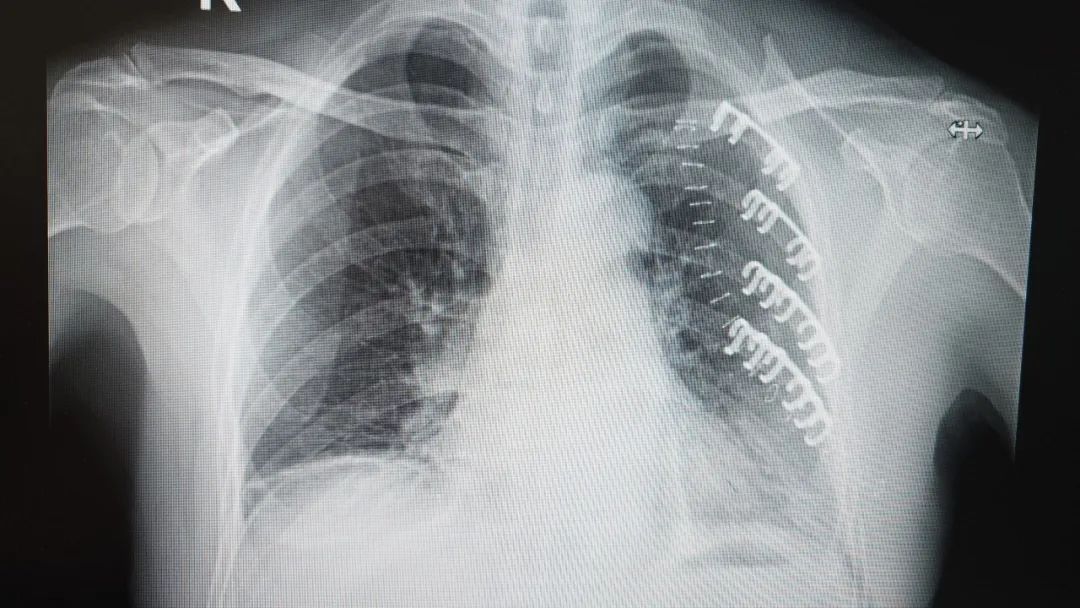

【技术领航】72岁老人摔断6根肋骨命悬一线!市二院胸外科孙振教授团队助其快速重生!

夕阳西下,本该是悠闲归家的时刻,对72岁的李大爷来说却成了惊魂瞬间。下午4点,他像往常一样骑着自行车,不料途中突发意外,连人带车重重摔倒在地!剧痛瞬间从左胸蔓延开来,李大爷面色痛苦,不仅无法动弹,胸闷、气促的感觉更让他喘不过气,120紧急将他送至葫芦岛市第二人民医院急诊科。